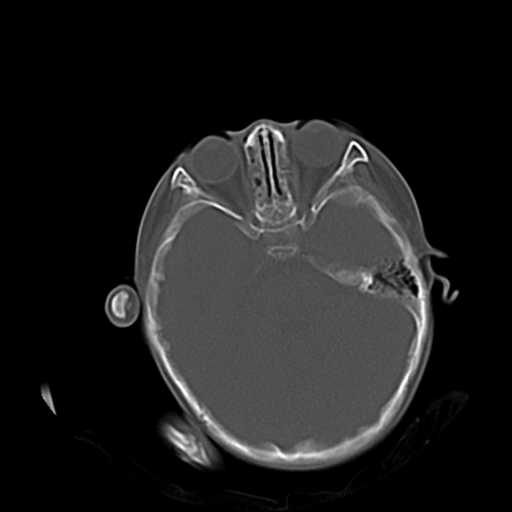

2.左侧上颌窦后壁部分骨质缺损,内有一牙齿样高密度,周围似乎无明显囊肿形成(没有继续往下扫描,而且只有骨窗,不便观察)。暂考虑左侧上颌窦牙源性囊肿可能。

3.小脑以及右侧颞叶无明显异常,颅盖以及颅底诸骨未见明显骨折,双侧枕骨内板蛛网膜粒压迹多、略深。

右侧颅底后可疑颅窝骨折.

双侧双颌窦及筛窦内可见密度增高影,考虑付鼻窦炎,上颌窦后壁骨折.